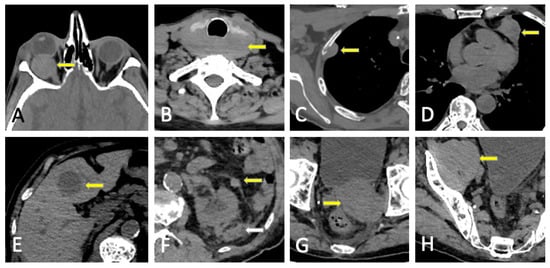

8. Pitfalls and Differential Diagnosis

8.1. Diffuse Imaging Findings

8.2. Malignant Focal Lesions

8.3. Benign Entities

9. Complications

- Abdel Razek, A.A.K.; Castillo, M. Imaging Appearance of Primary Bony Tumors and Pseudo-Tumors of the Spine. J. Neuroradiol. 2010, 37, 37–50. [Google Scholar] [CrossRef] [PubMed]

- Rodallec, M.H.; Feydy, A.; Larousserie, F.; Anract, P.; Campagna, R.; Babinet, A.; Zins, M.; Drapé, J.-L. Diagnostic Imaging of Solitary Tumors of the Spine: What to Do and Say. RadioGraphics 2008, 28, 1019–1041. [Google Scholar] [CrossRef]

- Hall, M.N.; Jagannathan, J.P.; Ramaiya, N.H.; Shinagare, A.B.; Van Den Abbeele, A.D. Imaging of Extraosseous Myeloma: CT, PET/CT, and MRI Features. Am. J. Roentgenol. 2010, 195, 1057–1065. [Google Scholar] [CrossRef]

- Varettoni, M.; Corso, A.; Pica, G.; Mangiacavalli, S.; Pascutto, C.; Lazzarino, M. Incidence, Presenting Features and Outcome of Extramedullary Disease in Multiple Myeloma: A Longitudinal Study on 1003 Consecutive Patients. Ann. Oncol. 2010, 21, 325–330. [Google Scholar] [CrossRef]

- Cho, R.; Myers, D.T.; Onwubiko, I.N.; Williams, T.R. Extraosseous Multiple Myeloma: Imaging Spectrum in the Abdomen and Pelvis. Abdom. Radiol. 2021, 46, 1194–1209. [Google Scholar] [CrossRef]